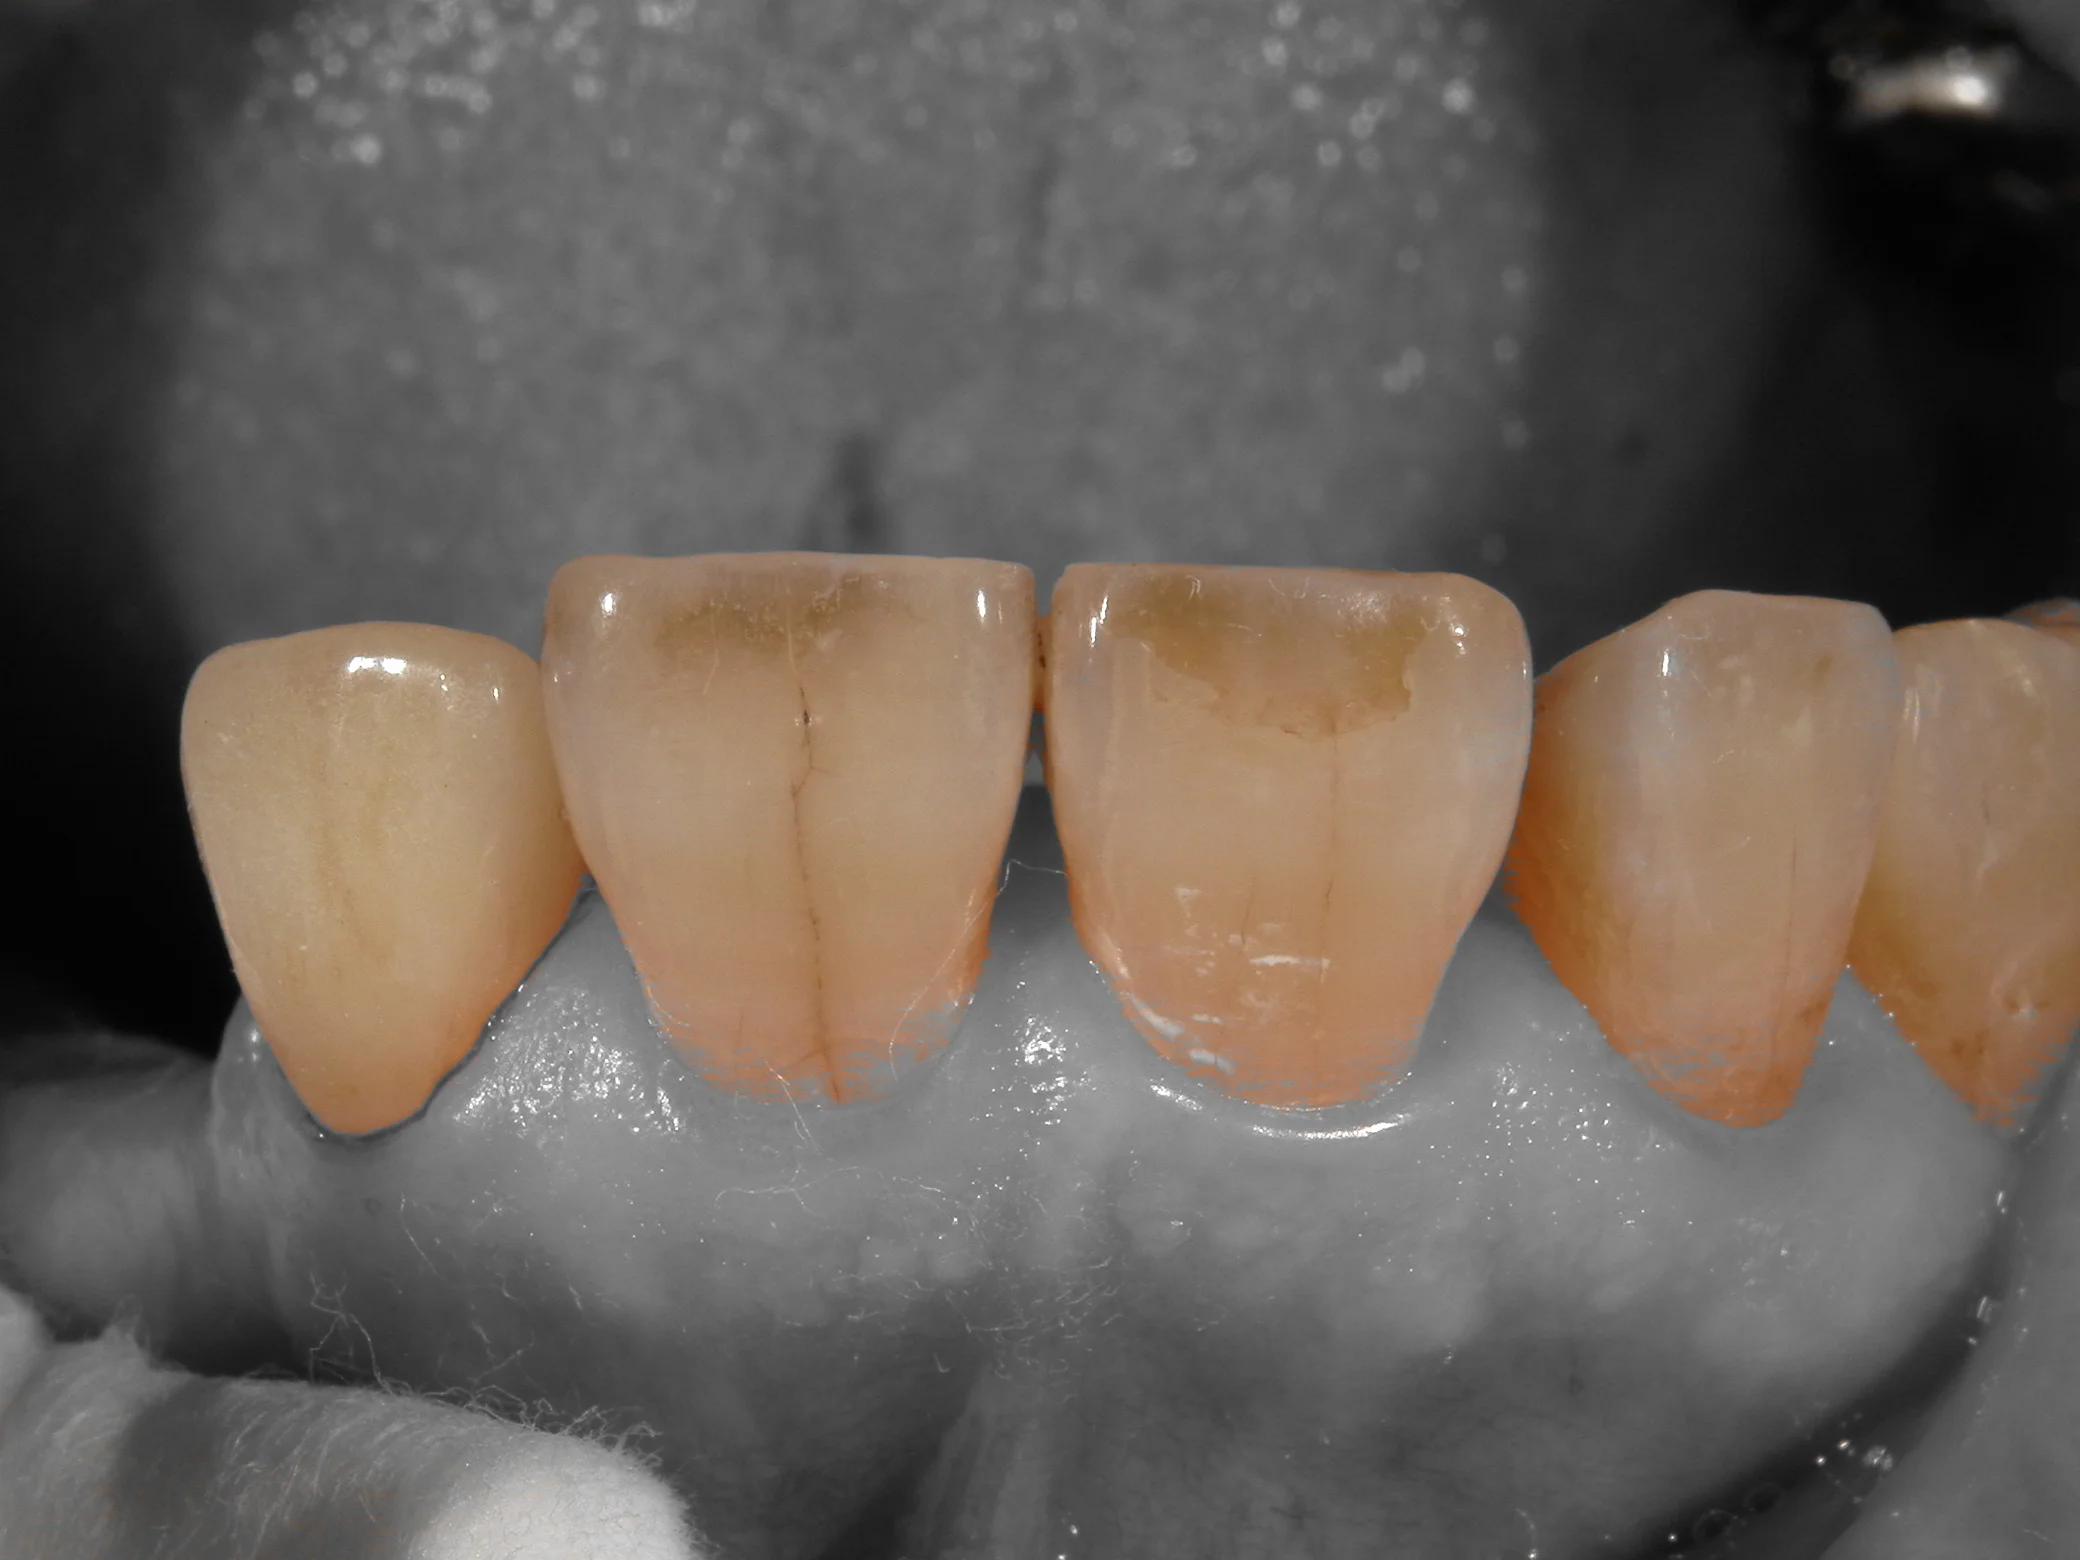

これをカメラの機能であるシェード抽出機能を用いて撮影するとこうなります。

歯の色だけピックアップしてくれるので、前後の歯と色を合わせやすいんですね。